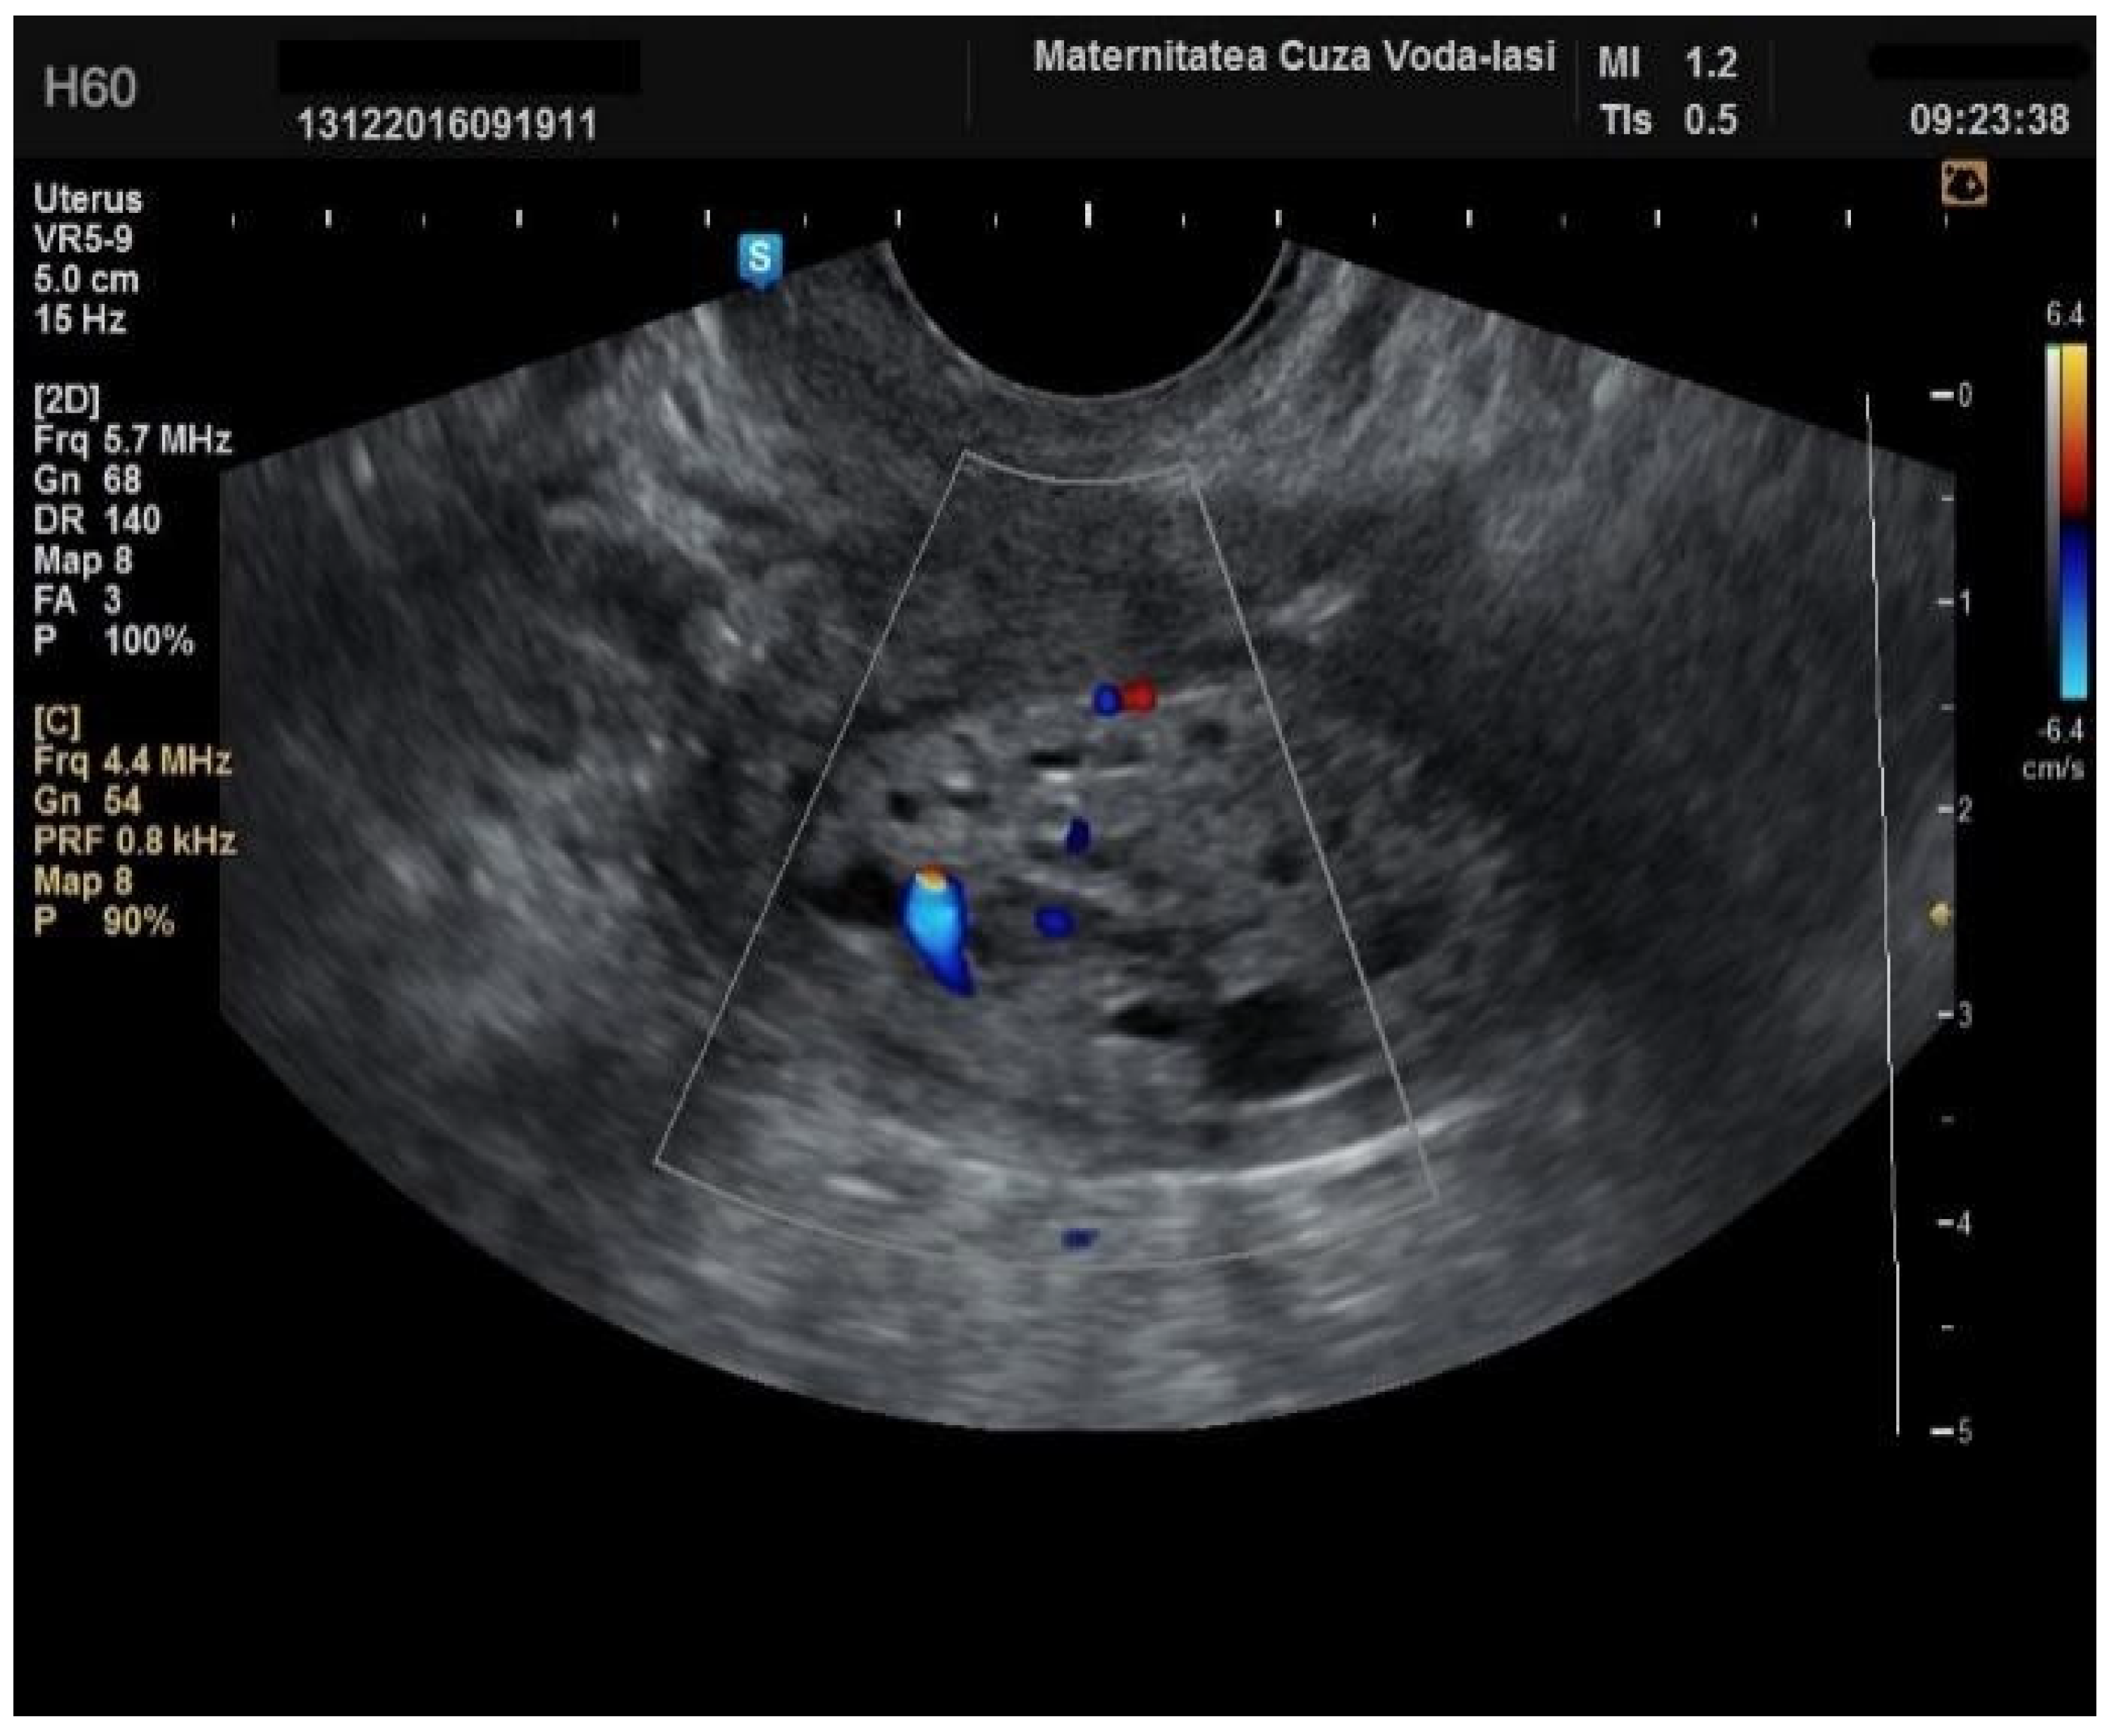

Figure 9. Color Doppler vascular score 4 in endometrial cancer.

Regarding the color Doppler assessment, a vascular score of 1 usually excludes endometrial cancer, with a sensitivity of 87.5% and a specificity of 79% (Figure 8). This is due to the presence of a high number of newly formed vessels in malignant tumors (Figure 9).

Furthermore, color Doppler imaging proved valuable in more accurately determining myometrial invasion. The predominant feature of blood vessels in endometrial cancer was the presence of scattered vessels (Figure 10), which demonstrated a sensitivity of 50% (95% CI: 0.2152 to 0.7848) and a specificity of 94.74% (95% CI: 0.8563 to 0.9819). Additional vascular aspects indicative of endometrial cancer were the presence of vessels with various branches (Figure 11) and color splashes (Figure 12).